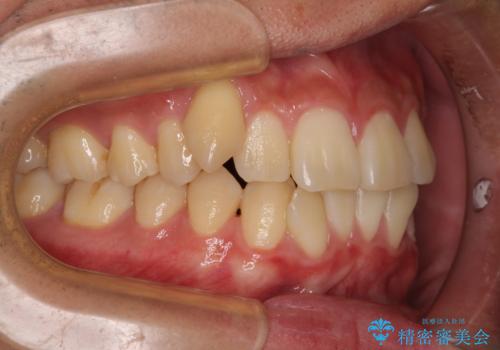

- 前歯のデコボコと右上の八重歯を気にして来院された患者様です。

マウスピース矯正とワイヤー矯正で悩んでいらっしゃいましたが、非常に強い咬合力であることや、お仕事柄不規則な生活リズムになることが多いとのことで、ワイヤー装置にて矯正治療を行うこととしました。